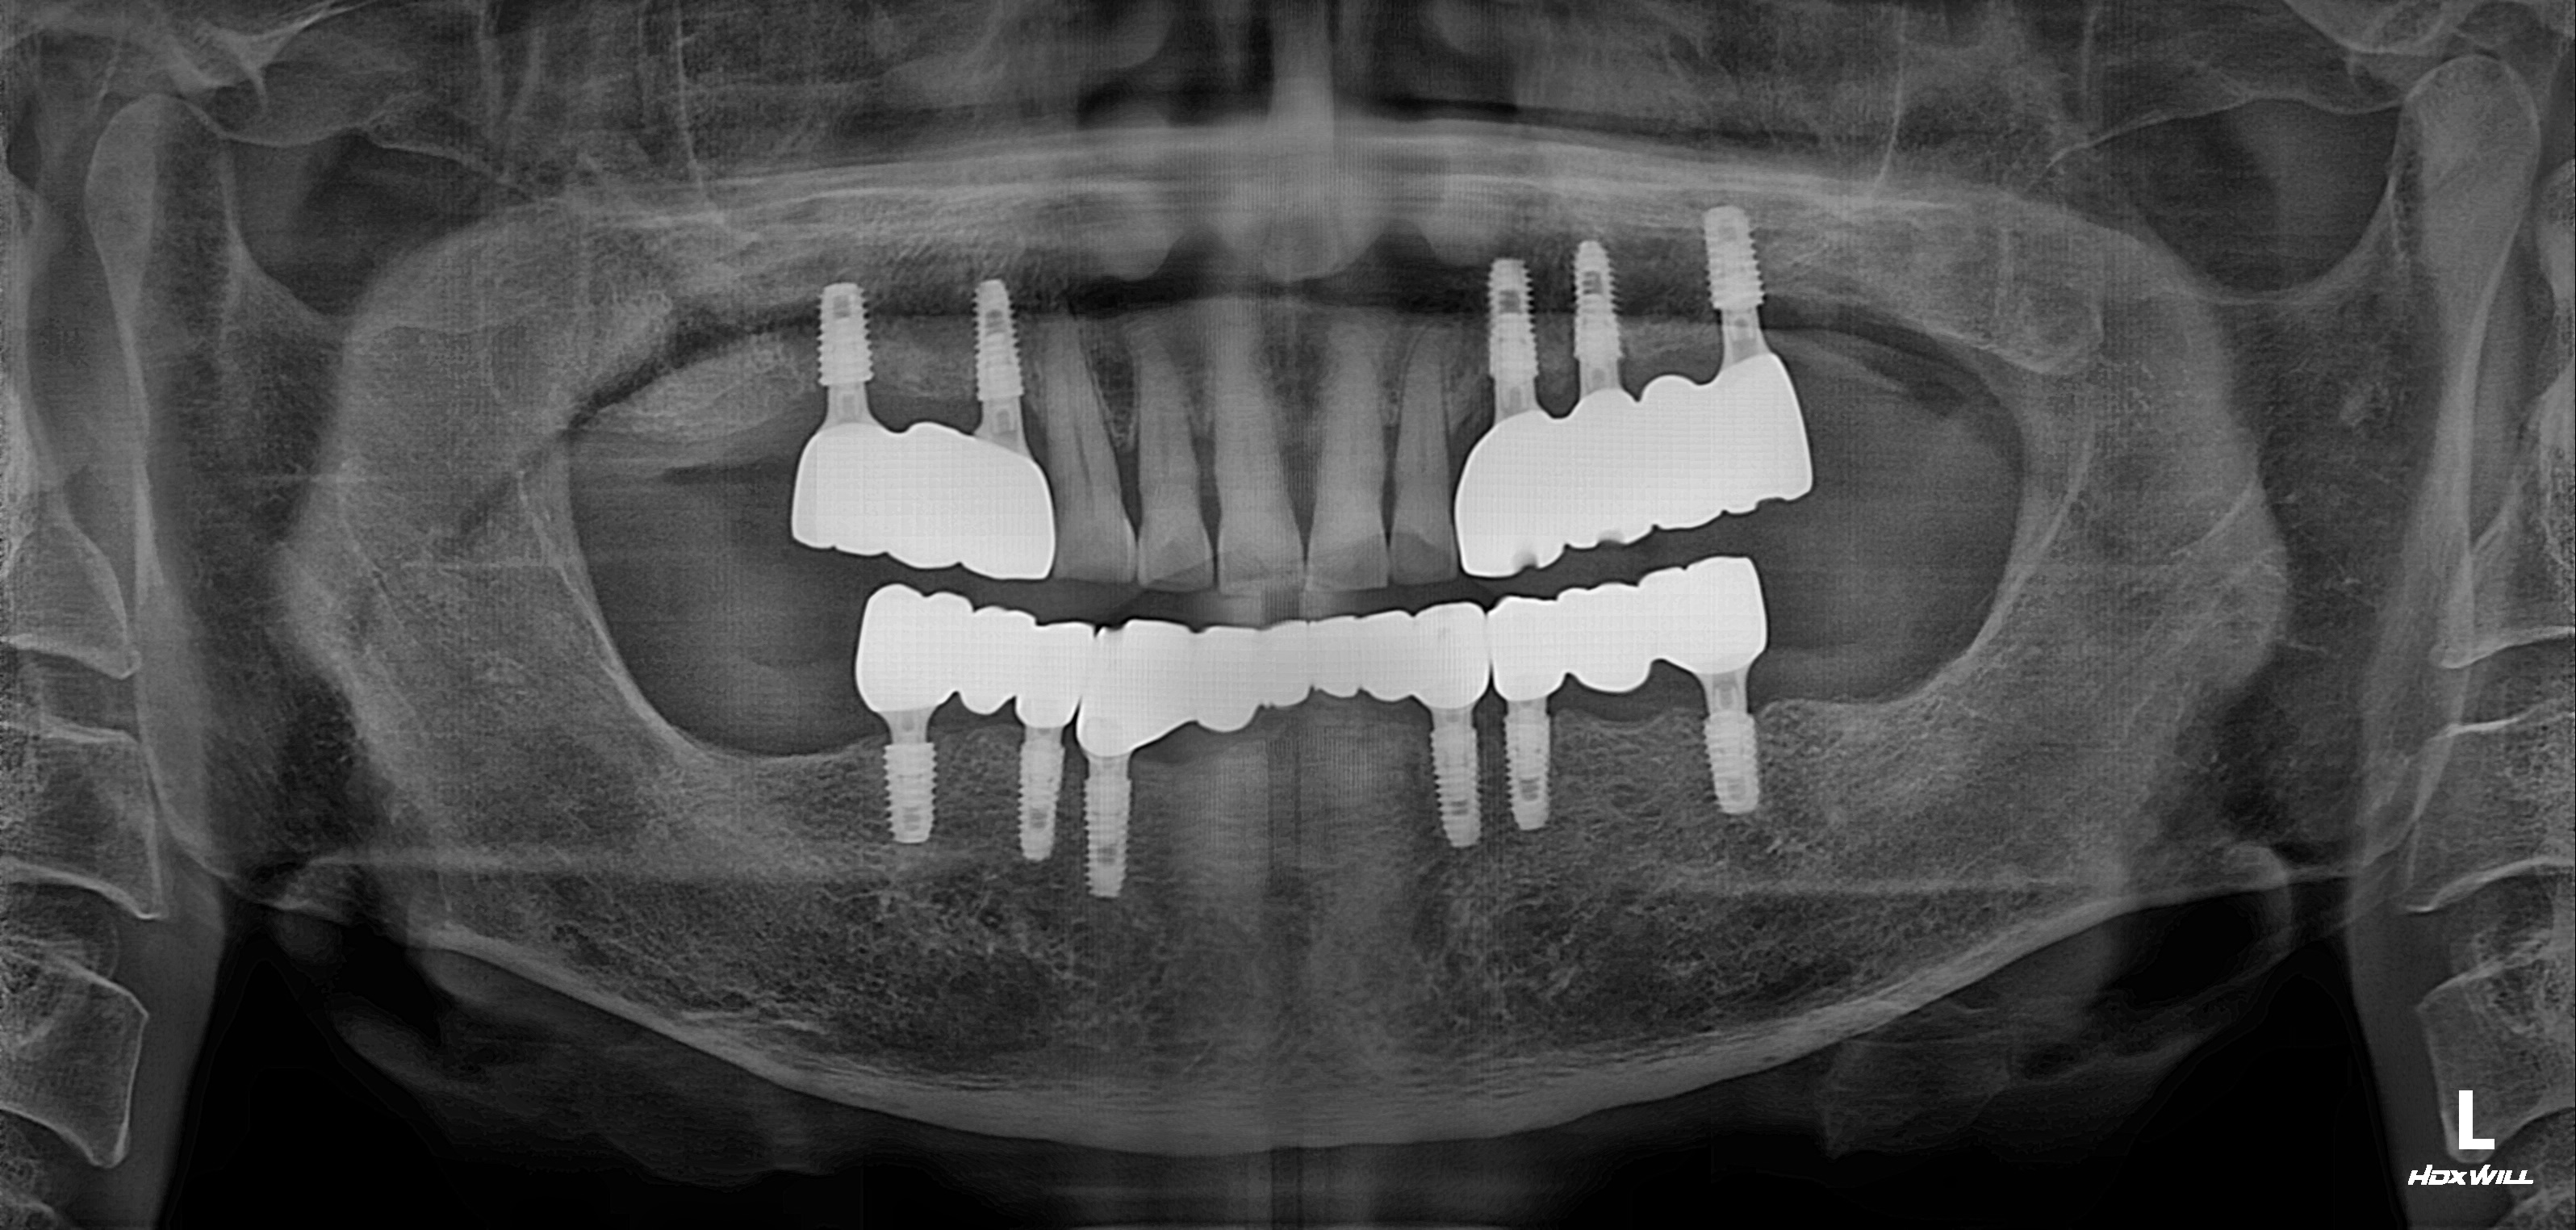

하악 전체+상악 구치부 임플란트 식립사례

전후사진